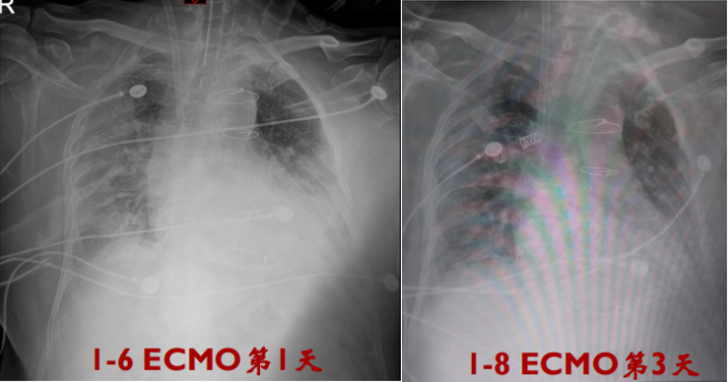

患者氧合仍差,PFR 40~70 mmHg,潮气量700~800 ml。与家属充分沟通后行VV-ECMO治疗:股静脉23 F引流,颈内静脉17 F灌注,转速3570 rpm,流量4.68 L/min,呼吸机PCV:PC 12 cmH2O,PEEP 8 cmH2O,RR 15次/min,FiO2 0.5,实测潮气量300 ml左右、RR 20次/min左右。

入MICU第68情况1月8日-10日

呼吸机PCV:PC 12 cmH2O,PEEP 8 cmH2O,RR 12次/min,FiO2 0.4~0.6,实测潮气量350~600 ml,RR波动于20次/min左右。

ECMO:转速2500~3000 rpm,流量2.9~3.9 L/min,气流量3 L/min。

多次查血气分析:PaO70~100 mmHg,PaCO2正常范围内。肝功能正常,CRRT治疗中,肌酐等指标相对稳定。

1月9日复查胸部X线片可见双肺密度较前增高。

评估呼吸功能:启动ECMO后,FiO2 1.0,pH 7.34,PaCO2 32.3 mmHg,PaO2 90.9 mmHg,Lac 0.9 mmol/L。影像学表现较前加重,实变影增多(图4)

图4  我院床旁胸片(2023年1月6日)

②氧合/影像学:胸部X线片可见ECMO第3天,炎症反应有所吸收(图5),在同等条件下,PaO2初始呈上升趋势,呼吸支持条件也逐渐下调。

图5  胸片复查对比